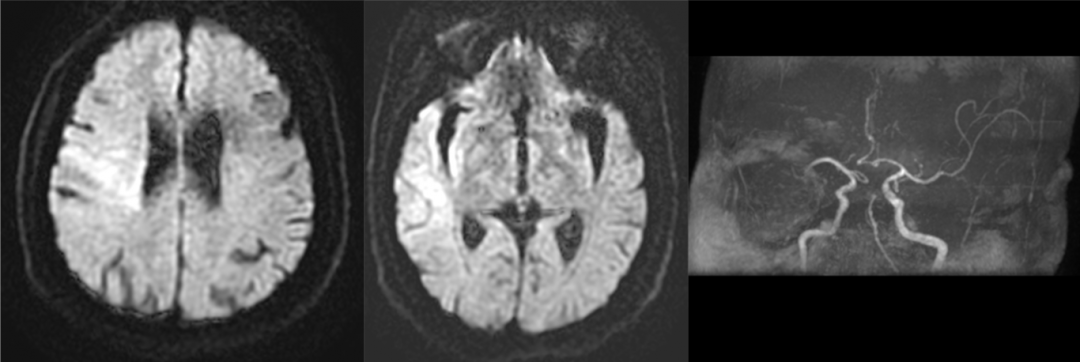

病例1:患者为69岁女性,因突发左侧肢体无力2小时来诊,既往心房颤动病史,入院时NIHSS评分16分,mRS评分4分,入院后头颅CT未见出血,予静脉溶栓治疗,效果不佳,绿色通道头颅核磁提示右侧半球大面积脑梗死,右侧大脑中动脉急性闭塞。

术前核磁影像(右侧半球大面积脑梗死,右侧大脑中动脉急性闭塞。)